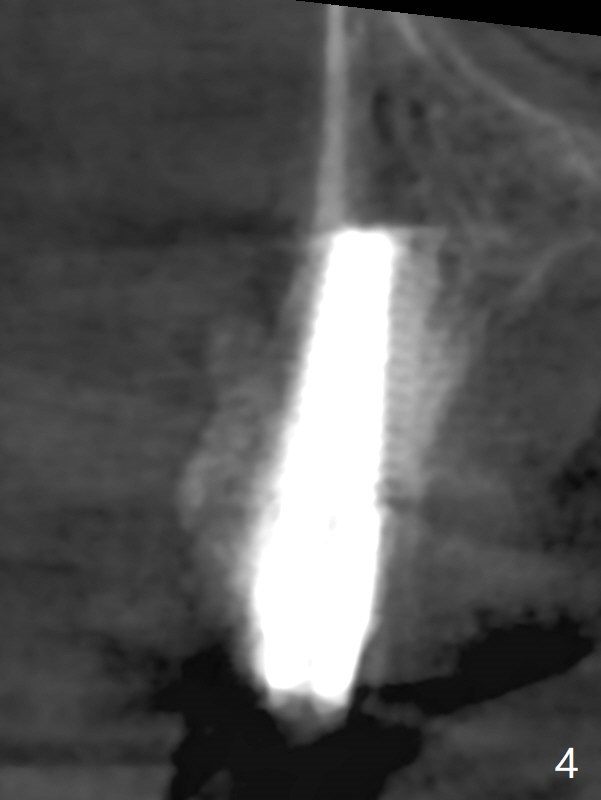

After extraction of the tooth #4 with fistula (Fig.1), the buccal bony defect is superior to the fistula. Before placement of a 4.5x17 mm tissue-level implant (Fig.2) and after osteotomy for bone-level one, PRF and mixture of autogenous bone and allograft are pushed from the socket through the buccal defect for repair (Fig.3 arrowheads). The trajectory of the implant (Fig.4) is consistent with design (Fig.5). The fistula reduces in size and in redness, while the apical elevation (as related to the underlying bone graft) remains prominent 13 days postop (Fig.6,7 *). The distal defect has been apparently repaired 9 months postop (Fig.8 *, as compared to immediately post bone graft in Fig.2). The distal defect has been apparently repaired 9 months postop (Fig.8 *, as compared to immediately post bone graft in Fig.2). The fistula disappears (Fig.9).